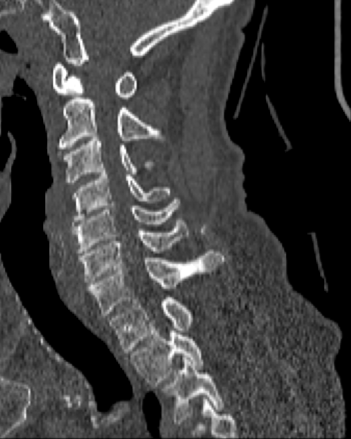

4.2 Vertebral Localization and Segmentation

We evaluated the model on the test sets from the VerSe2019 and VerSe2020 datasets. These test sets contain 113 subjects in total. Each CT volume was pre-processed by smoothing with a Gaussian kernel with σ\sigma = 0.75 mm to reduce noise.

The models have 22.91 million parameters for spine localization, 21.13 million parameters for vertebrae localization, and 17.19 million parameters for vertebrae segmentation. The inference time varies with the field-of-view and the number of visible vertebrae in the CT volume. All experiments were conducted on a dual-socket Intel® Xeon® Platinum 8462Y+ system (64 physical cores, 2.80 GHz, 120 MiB L3 cache) running Linux. On the combined test set of 113 subjects, the average inference time per volume was about 1 min 40 s. Specifically, the process took about 3 s for spine localization, 19 s for vertebrae localization, and 1 min 17 s for vertebrae segmentation. The visualization of vertebral localization and segmentation is shown in Figure 3.

(a) Original CT Image

(b) Segmentation Result

(c) 3D Mesh

Figure 3: Visualization of vertebral localization and segmentation results.